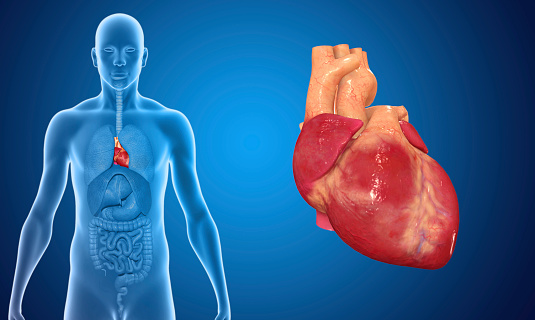

Si parla di prolasso della valvola mitrale (MVP) quando la valvola tra l’atrio ed il ventricolo sinistro del cuore non chiude perfettamente nel momento in cui il muscolo cardiaco si contrae. Una condizione di questo tipo può portare alla perdita di sangue che torna indietro nell’atrio. In questo caso il termine corretto è “rigurgito della valvola mitrale”. Nella maggioranza dei casi un prolasso di questo tipo non è pericoloso e non richiede cure o terapie particolari, fatta qualche eccezione. Cerchiamo di comprendere meglio.

Un soffio al cuore è clinicamente parlando un sintomo, segno di un passaggio molto intenso di sangue. Si distinguono due tipi di soffi al cuore, quello definito innocente e quello “anormale”. Nella stragrande maggioranza dei casi si tratta del primo tipo che è assolutamente innocuo. Ma non bisogna trascurare quelle ipotesi di “mormorio anomalo al cuore”. Ecco come.

Cos’è una stenosi della valvola aortica? Con questo termine si indica in medicina ed in particolare in cardiologia un restringimento della valvola aortica, punto di congiunzione fondamentale tra l’aorta ed il cuore: tale restringimento che può essere più o meno grave, impedisce alla valvola di aprirsi completamente, il che ostacola il flusso di sangue dal cuore all’aorta e al resto dell’organismo, aumentando il rischio di incappare in un accidente cardiovascolare. Quando questa valvola è eccessivamente ostruita, limitata, il cuore deve lavorare più intensamente per pompare il sangue all’organismo, il che alla lunga può portare ad un indebolimento del muscolo cardiaco. Per tale motivo una stenosi grave solitamente comporta l’intervento chirurgico di sostituzione della valvola. Scopriamone cause e sintomi.

Si parla di soffio al cuore quando, con auscultazione tramite lo stetoscopio, si evidenzia un rumore anomalo (tipo sibilo/fruscio) tra un battito cardiaco e l’altro. Soffi cardiaci possono essere presenti alla nascita (congeniti) o svilupparsi più tardi nella vita. Un soffio al cuore non è una malattia, ma a volte è indicativo di un problema. Nella maggior parte dei casi i soffi cardiaci sono innocui ( e per questo definiti innocenti) e non necessitano di cure. Può essere comunque utile monitorarli, proprio per identificare o escludere una malattia cardiaca sottostante che potrebbe essere pericolosa. Il trattamento, se necessario, è diretto a causa. Scopriamo insieme quali sono queste cause e se esistono sintomi specifici.